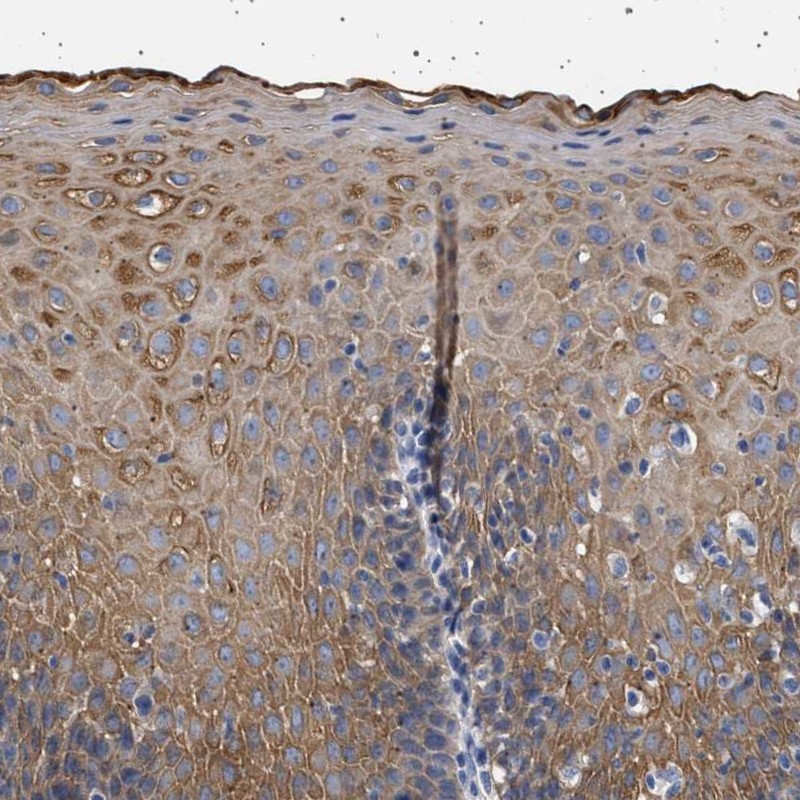

Immunohistochemical staining of human esophagus shows moderate cytoplasmic positivity in squamous epithelial cells.